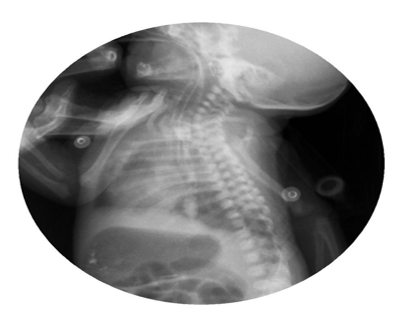

Abdominal radiographs showed persistent severe distension of the gastric chamber despite high caliber tube drainage and evidence on one occasion of bubbling of the same so tracheoesophageal fistula was suspected. Barium esophagogram was performed with evidence of complete passage into esophagus, stomach and pylorus, without a fistulous tract (Figure 1). However, due to persistent symptoms, bronchoscopy was performed to rule out congenital malformation of the airway, H-type tracheoesophageal fistula of 3 mm in diameter located 5 rings above the carina was visualized, nevertheless, endoscopic or surgical correction at this time was not possible due to hemodynamic instability (Figure 2).

Figure 1 Barium contrast esophagogram with no evidence of fistulas or extrinsic compressions. Normal.